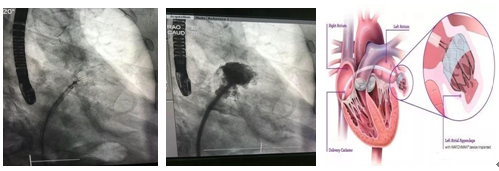

此次接受左心耳封堵术的患者为77岁老年男性,因“冠心病,慢性心力衰竭,心房颤动,慢性肾功能不全,轻度贫血”于我科就诊,3年前患者曾在我院行冠脉造影+前降支支架植入术,入院时心脏彩超提示全心扩大,左室射血分数40%,患者合并慢性肾功能不全,肌酐清除率为21.8ml/min,并有间歇性大便隐血阳性。入院后给予纠正心衰等积极治疗,患者大便隐血逐渐好转,因患者存在慢性心房颤动,卒中风险CHA2DS2-Vasc评分4分,出血风险HAS-BLED评分4分,房颤卒中风险较高,根据指南需要抗凝治疗;但患者出血风险也为高危,如长期抗凝大出血风险亦较高。经过科室讨论并与患者及家属沟通交流后,殷跃辉教授决定为患者实施左心耳封堵术。经过缜密的准备,2018年6月14日上午,在殷跃辉教授的指导下,凌智瑜副教授、杜华安主治医师在超声科朱叶峰、苏蕾主治医师以及麻醉科医师的密切配合下为患者成功实施了左心耳封堵术。手术采用全麻,首先采用食道超声排除了左心耳血栓,穿刺右侧股静脉,并在食道超声及X线监测下穿刺房间隔。造影提示患者左心耳呈菜花状,远端分叶,开口28mm,属于容易发生血栓的左心耳形态。手术选用了33mm的Watchman封堵伞,在超声指导下精确定位于左心耳,造影提示完全覆盖左心耳开口,超声监测显示无明显残余分流,X线透视下牵拉试验显示封堵伞铆钉良好,成功释放后超声及造影均显示封堵良好,手术顺利完成。

左心耳封堵术简介

研究表明非瓣膜型房颤患者中89%的血栓来自于左心耳,瓣膜型房颤为44%,通过封堵左心耳来预防房颤时在左心耳内血栓的形成,从而降低房颤患者由血栓栓塞引发长期残疾或死亡的风险,同时左心耳封堵术可消除部分肝肾功能不全的患者无法长期抗凝治疗的依赖性,为患者提供治疗的新选择,从源头解决房颤患者的中风威胁。